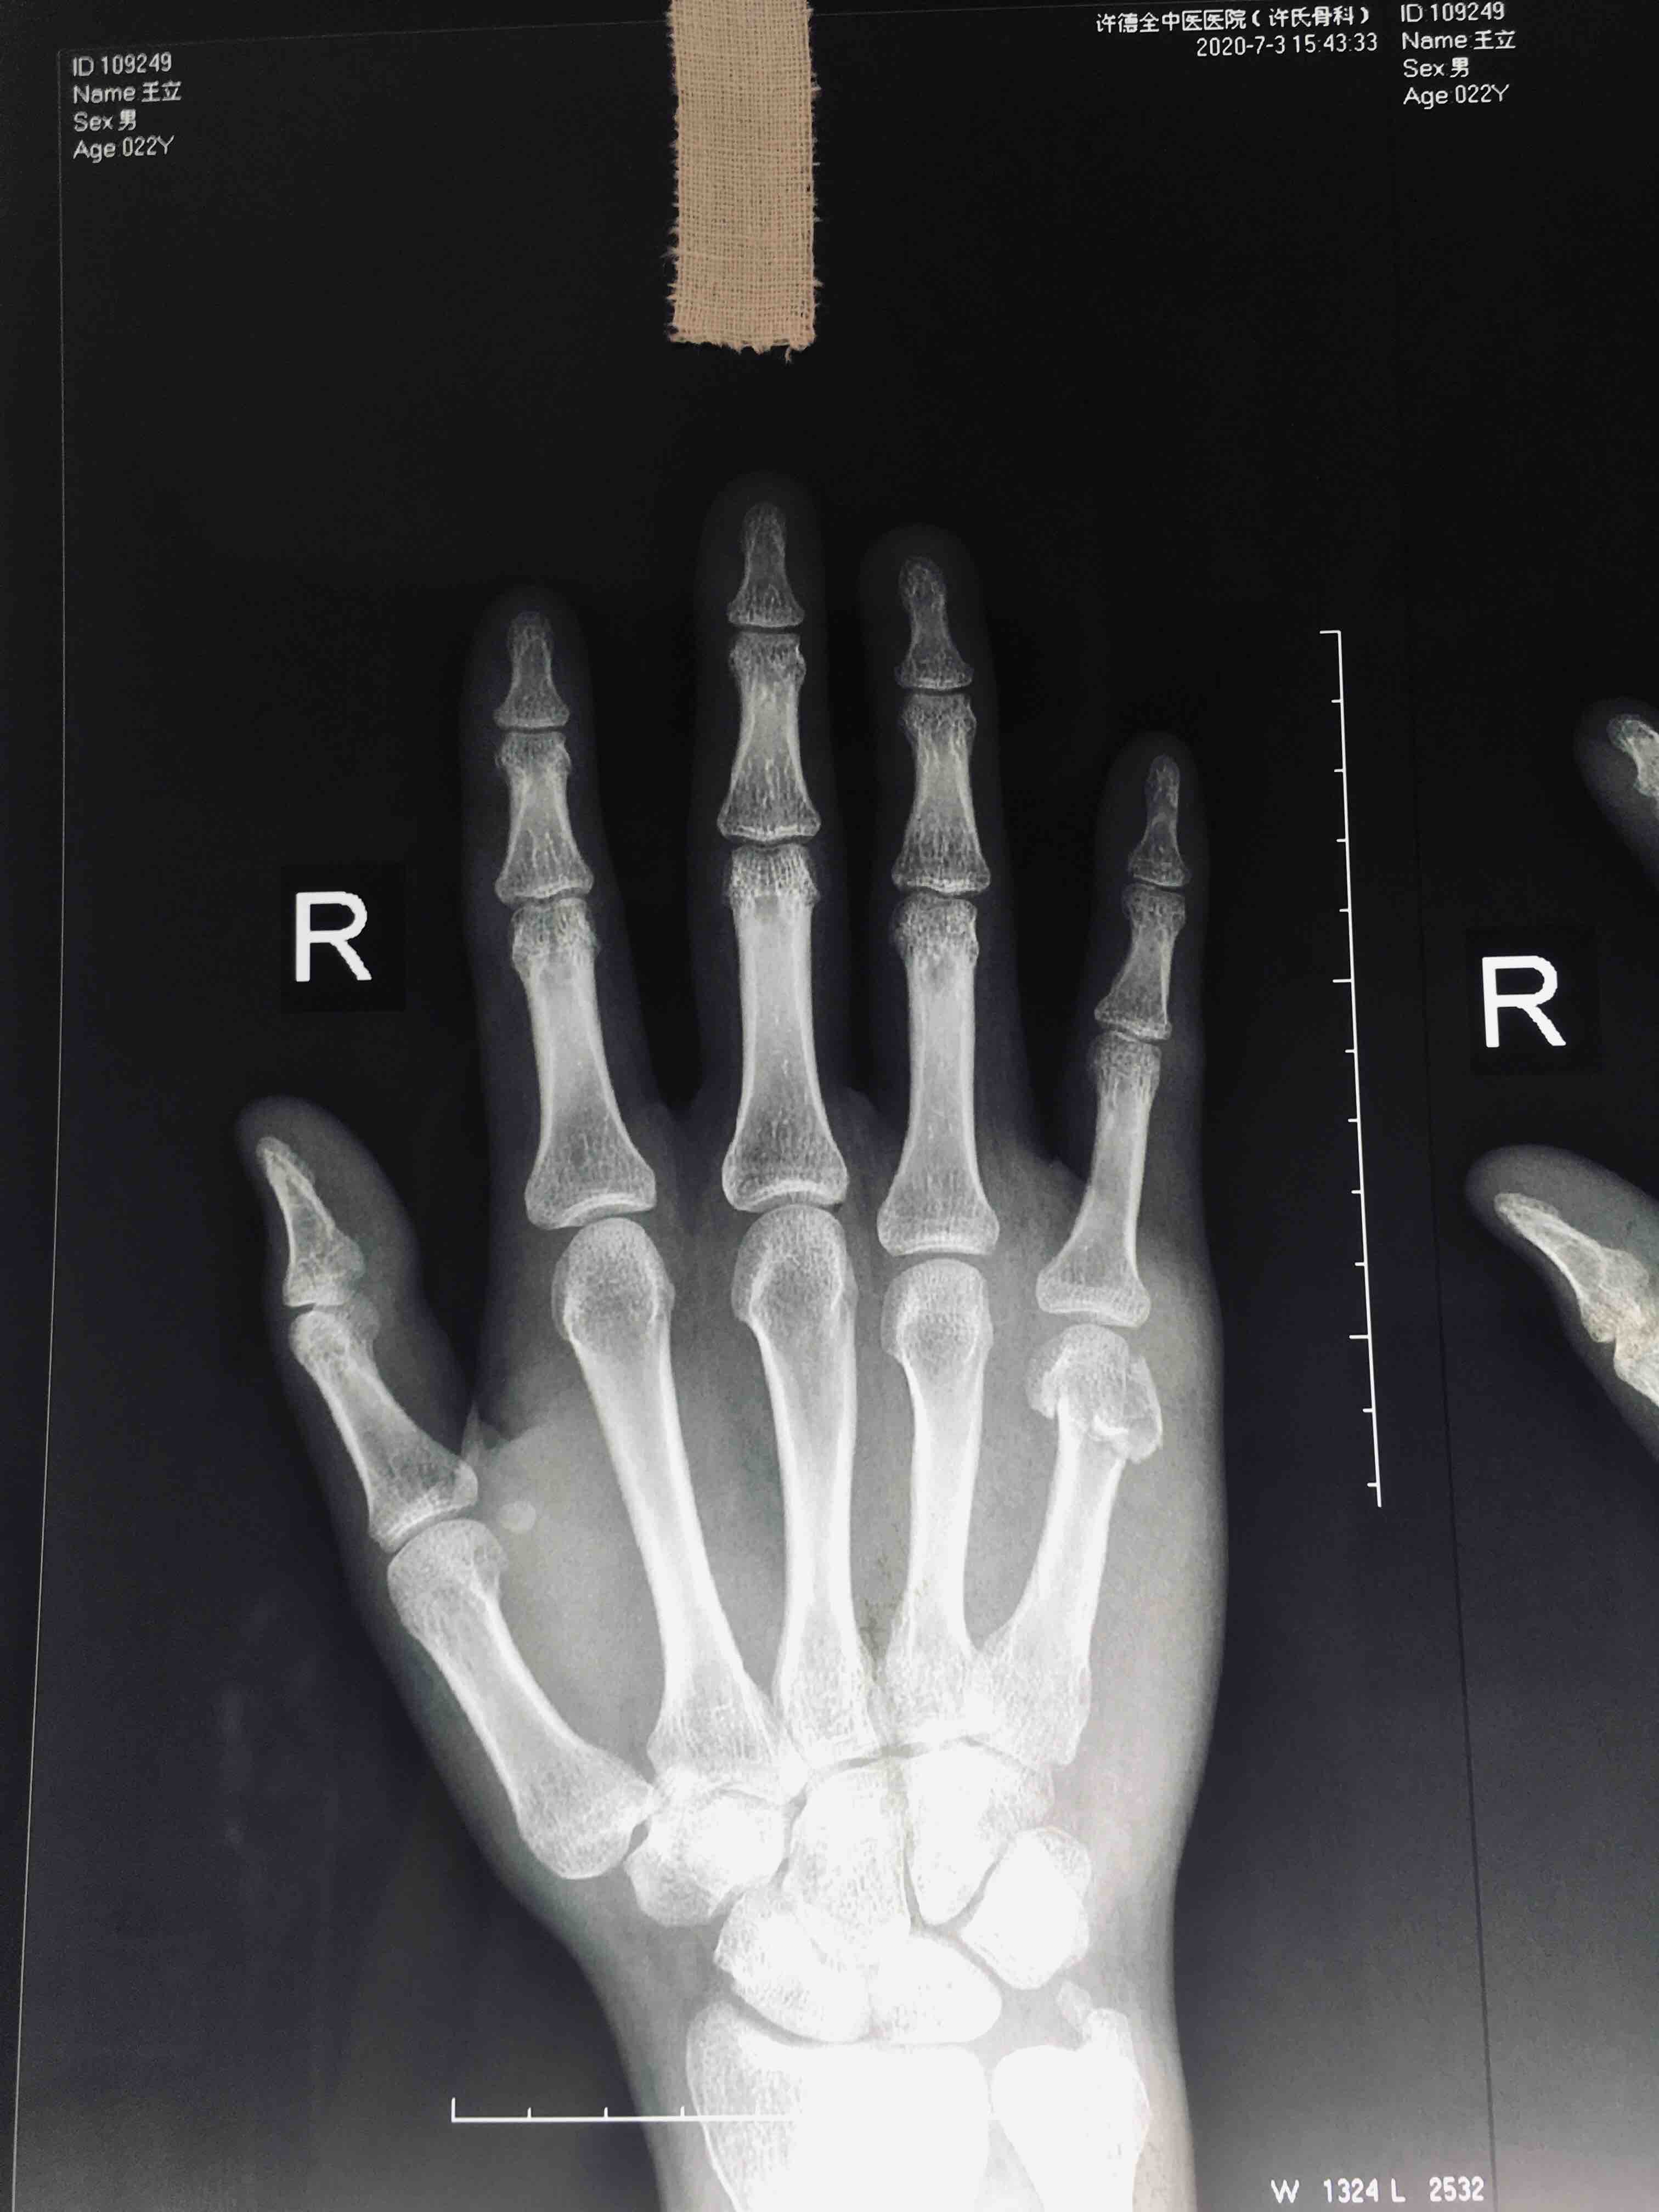

掌骨头粉碎性骨折(切复内固定术)

摔伤后右手疼痛1小时入院。既往因右手第五掌骨头骨折行闭合复位固定术。

右手第五掌指关节处肿胀,局部皮色皮温正常,压痛及纵向叩击痛阳性,末梢血运感觉正常,掌指关节活动受限。

臂丛麻醉下行切复内固定术,术后制动